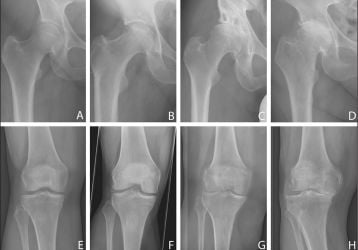

• Гонартроз — артроз коленного сустава. Чаще всего он встречается после 45 лет, хотя в последнее время заболевание «молодеет».

• Коксартроз — артроз тазобедренного сустава. Данная разновидность заболевания является лидирующей.

• Остеоартроз. Это хроническая прогрессирующая патология синовиальной части костного соединения. Она бывает генерализированной и локализованной.